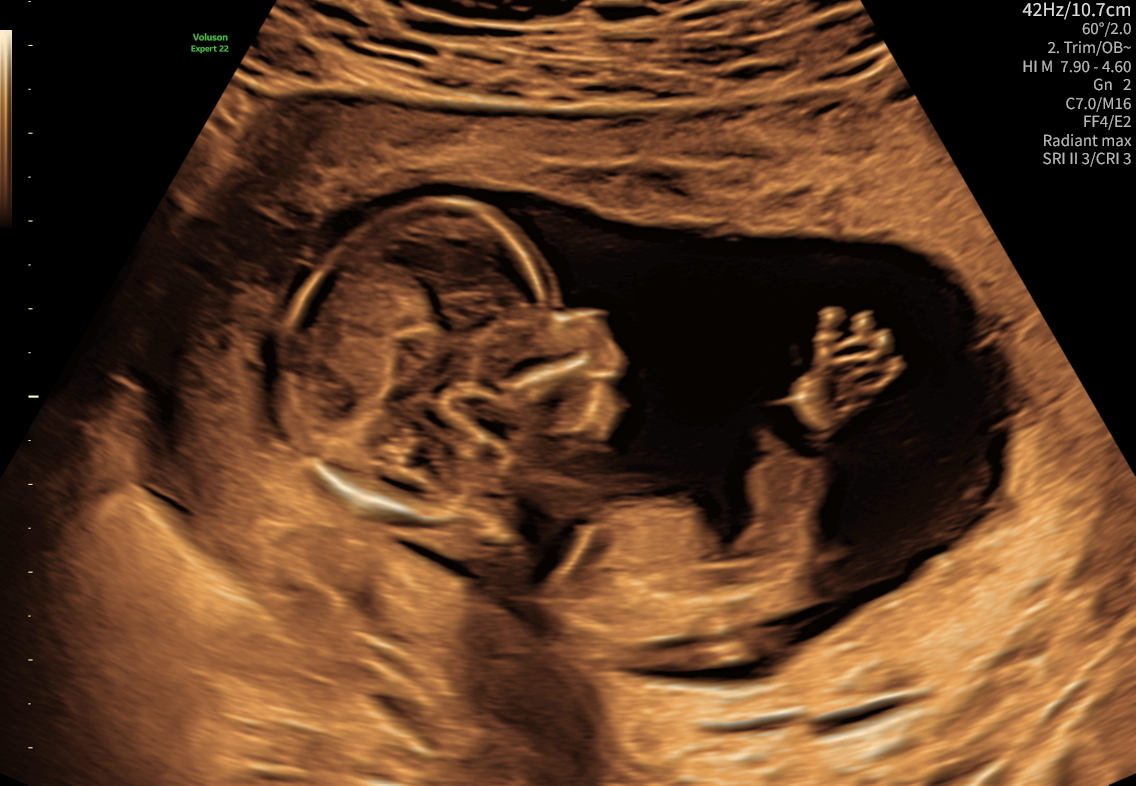

En tryghedsscanning giver dig ro i maven mellem de planlagte undersøgelser. Hos Centrumlægerne i Hillerød udfører autoriserede jordemødre en grundig scanning med hjertelyd, trivsel og vurdering af de vigtigste forhold i graviditeten.

- Barnets hjertelyd og bevægelser

- Vækstmåling og estimeret vægt

- Kontrol af fostervandsmængde

- Placering af moderkagen

- 3D/4D-scanning – uge 25–32